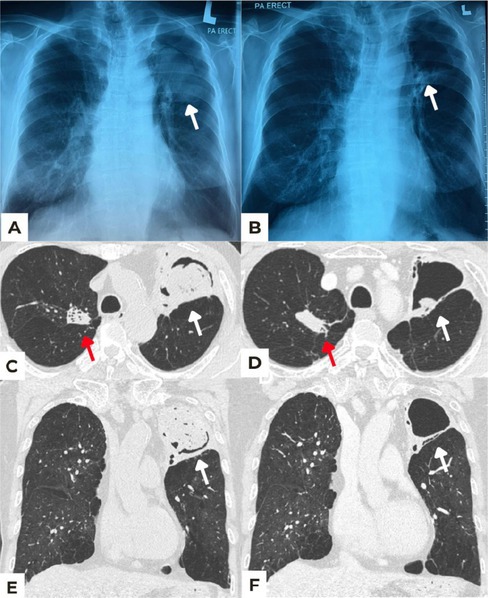

肺曲菌肿可引起危及生命的咯血。手术切除和/或支气管动脉栓塞(BAE)是公认的治疗方式,但这两种方法对有合并症的虚弱患者都有风险。曲菌瘤仅用抗真菌药物自行消退是罕见的。我们报告一位有肺结核病史的老先生,因左上叶曲菌瘤而咯血。考虑到风险,他拒绝了手术和BAE。口服伏立康唑,后给予依沙乌康唑治疗,6个月后临床改善,曲菌瘤大小明显减小。抗真菌药物可能是一个可行的治疗选择曲菌瘤患者不适合或谁拒绝更多的侵入性手术。需要进一步的研究来验证这种方法的有效性和安全性。

Pulmonary aspergilloma can cause life-threatening haemoptysis. Surgical resection and/or bronchial artery embolization (BAE) are established treatment modalities, but both can be risky in frail patients with comorbidities. Spontaneous regression of aspergilloma with antifungal agents alone is rare. We report an elderly gentleman with a background history of treated pulmonary tuberculosis, who presented with haemoptysis due to a large left upper lobe aspergilloma. He declined surgery and BAE due to perceived risks. Oral voriconazole and later isavuconazole were prescribed, which led to clinical improvement and significant reduction in the size of the aspergilloma over 6 months. Antifungal agents might be a viable therapeutic option for aspergilloma patients unsuitable or who declined more invasive procedures. Further studies are needed to validate the efficacy and safety of this approach.